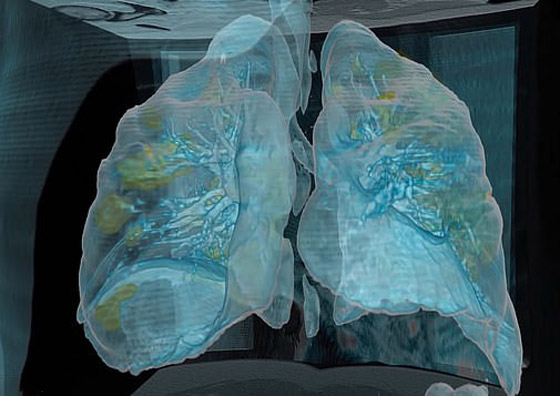

تصوير مقطعي محوسب من مستشفى جامعة جورج واشنطن يُظهر آثار فيروس كورونا المستجد، أو ما يُعرف بـ"كوفيد-19" رئتي رجل عمره 59 عاماً. فشاهدوا معنا في الفيديو المدهش أدناه كيف تبدو رئة مصاب بفيروس كورونا (فيروس كوفيد 19) وما يحصل داخلها..